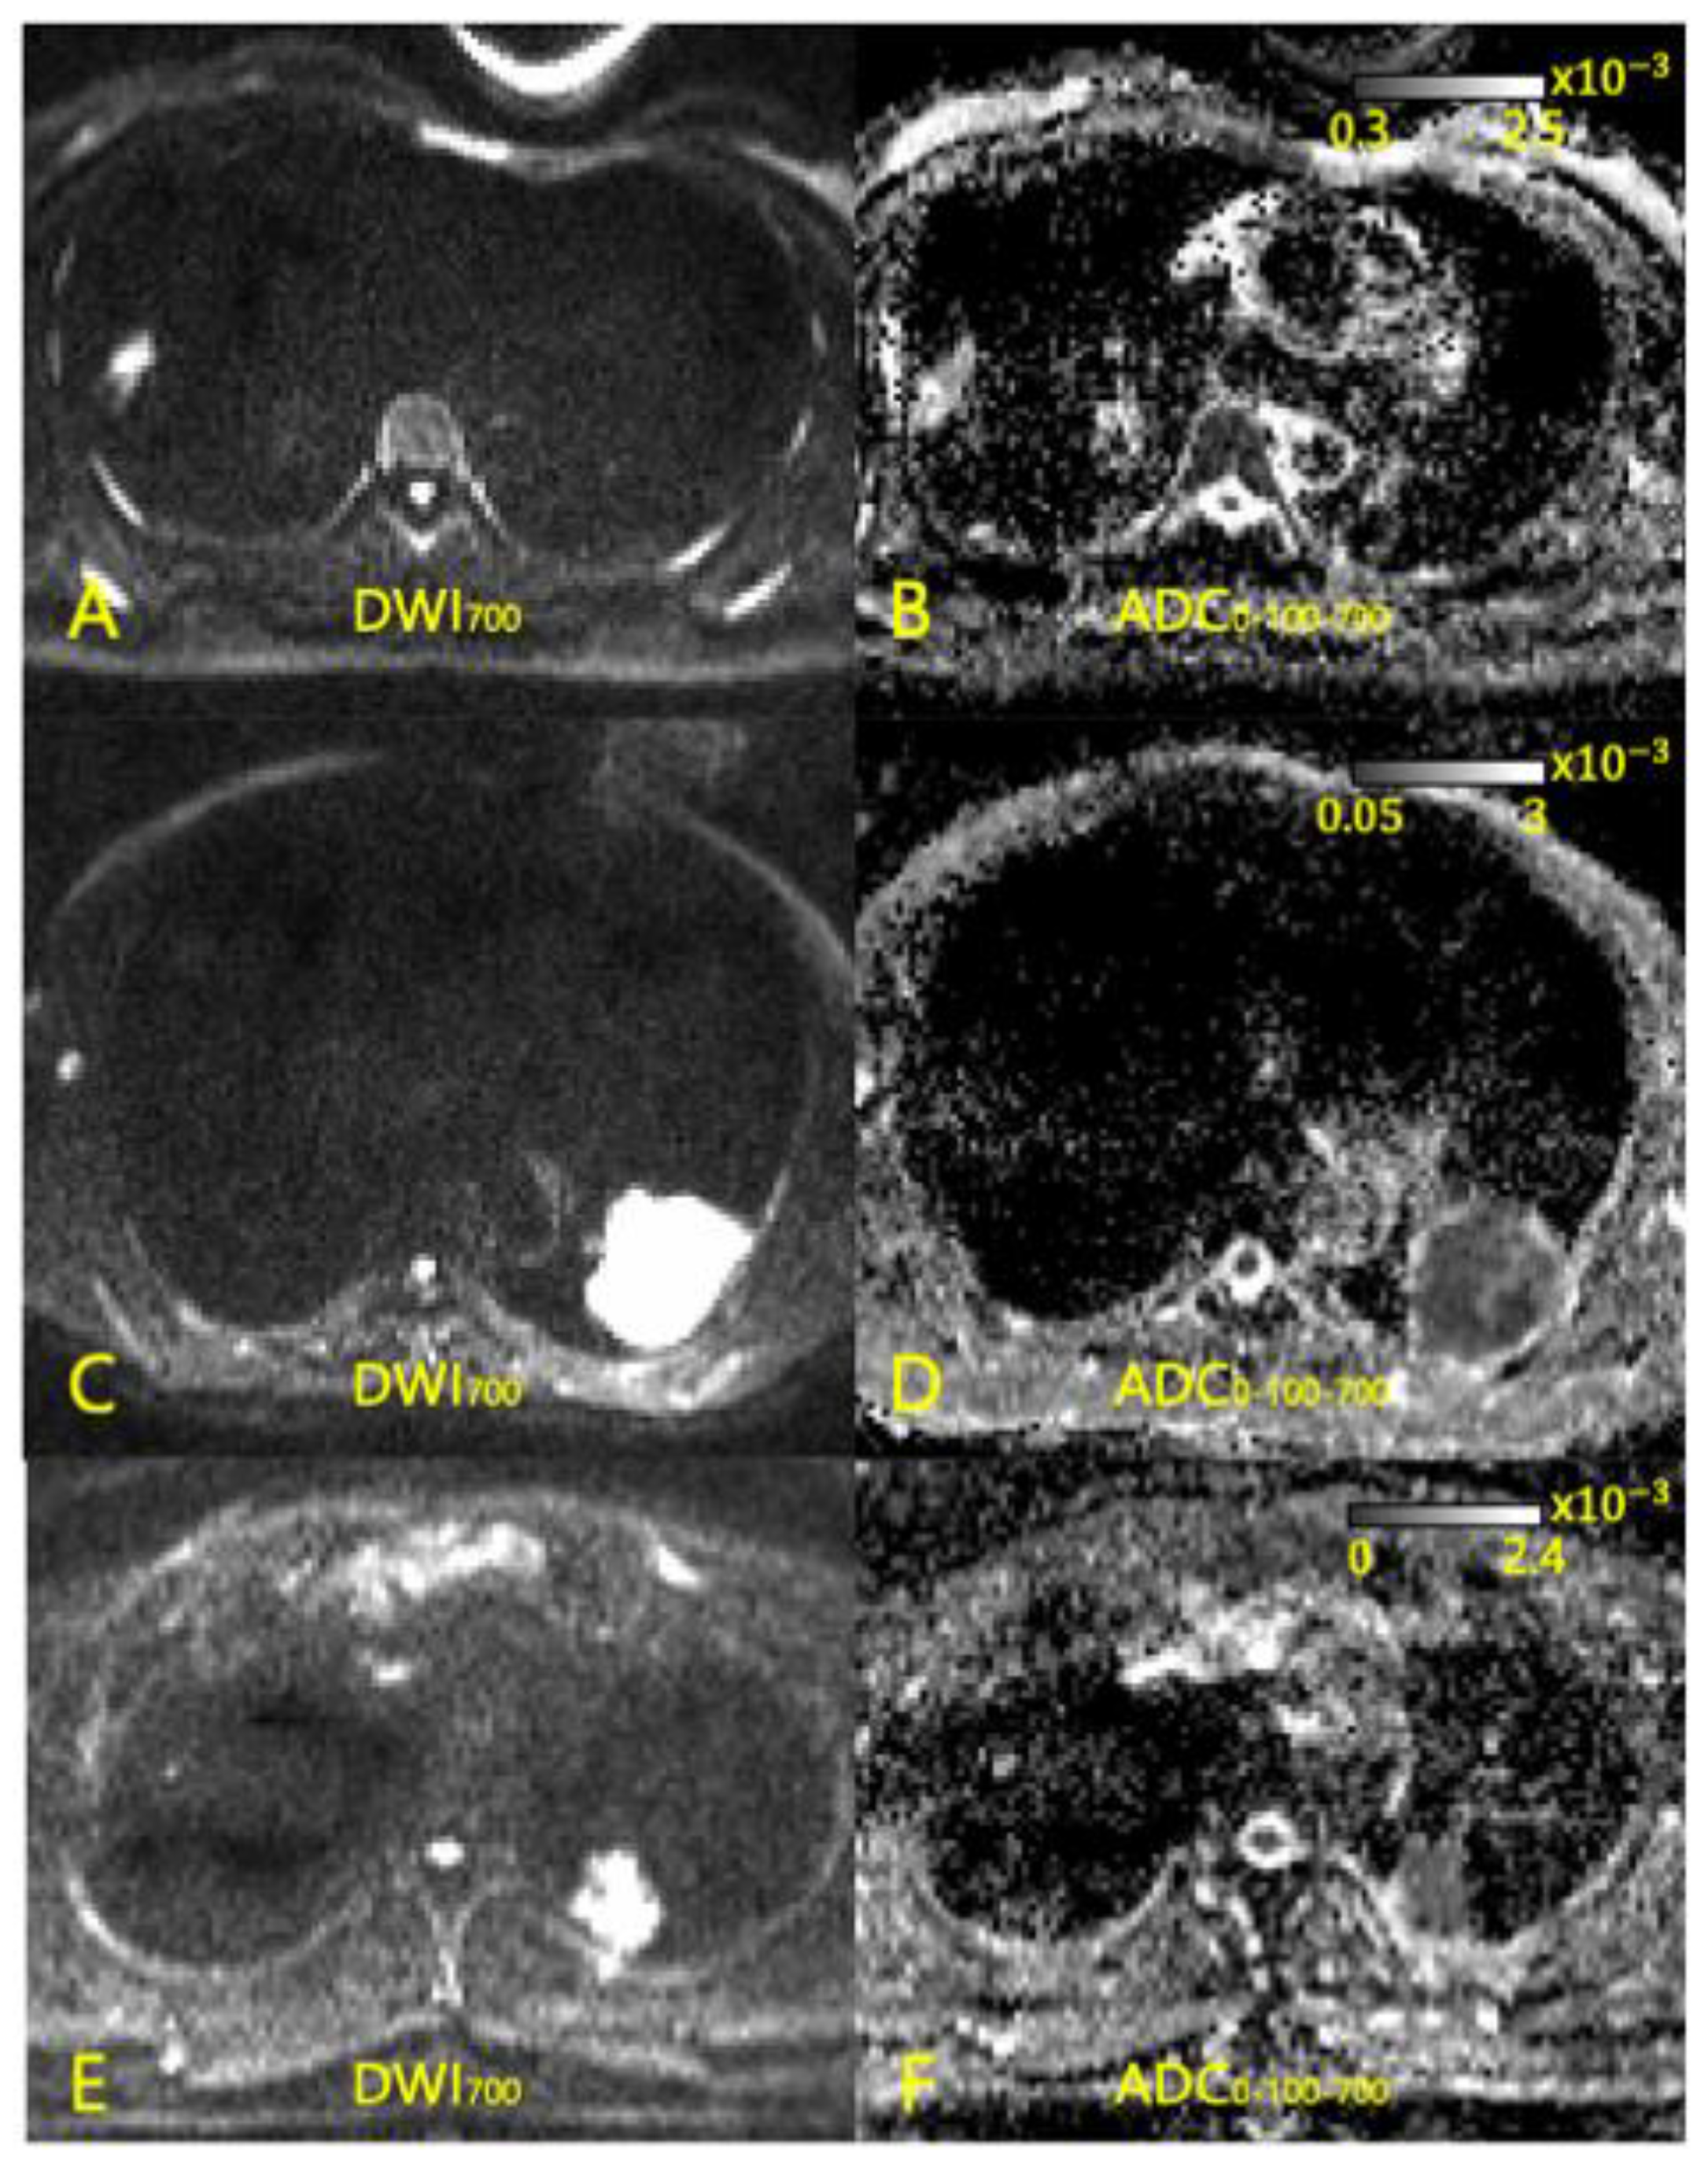

2.2. MR Acquisition

2.3. Image Processing